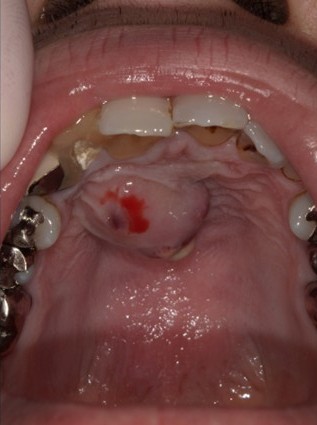

| 主訴 | 膿で腫れて痛みが強い、他の歯医者で抜歯しかないと言われ相談で来院 |

| 状態 | 自発痛もかなり強く、写真のように膿が溜まって腫れ上がっている状態 |

| 治療内容 | X写真から根先部の根先病変が原因と思われるため、根管治療を行った。 骨成長因子を用いて、骨の再生を促した。 結果、2年経過後病変の大きさが1/3まで縮小し、骨の再生が認められる。 本人も症状や違和感がなくなったため、一時的に補綴物をセラミックで行った。 |

| 料金 | 根管治療10万円、ファイバーコア2万円、EーMAX11.5万円 |